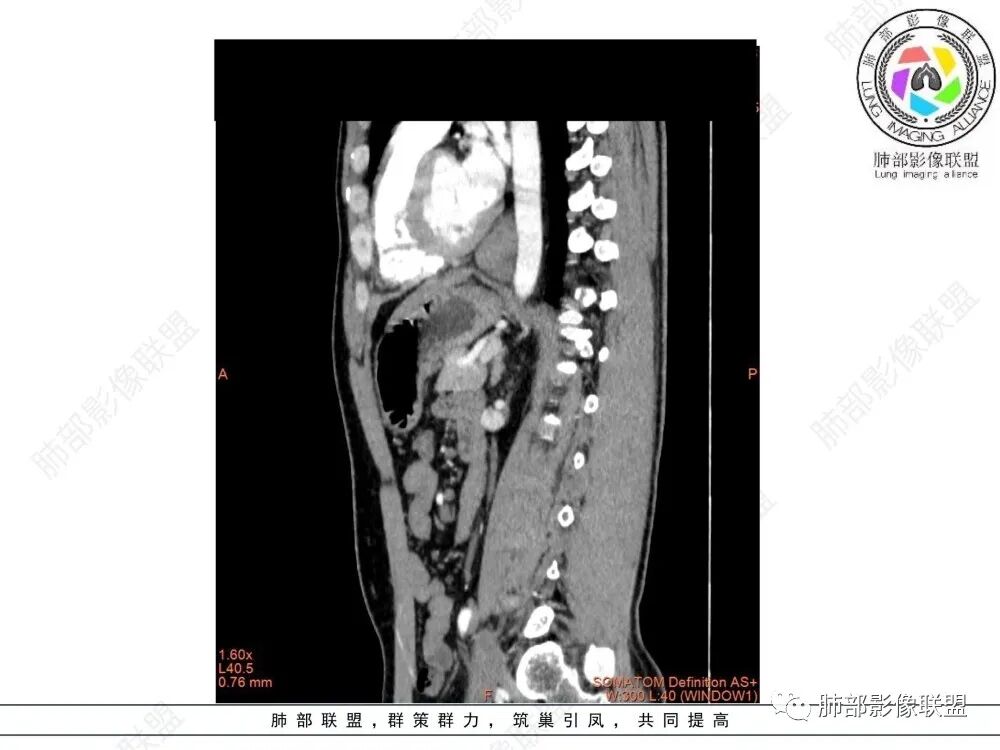

影像学特点:类纵隔区病变,沿食管生长,形态不规则,但边界清楚,内部信号/密度均匀,强化程度比较弱。

影像诊断思路:起源食管肿瘤(非黏膜起源,肌层起源),良性或低度恶性肿瘤可能性大,一般以神经鞘瘤、胃肠间质瘤及平滑肌瘤为主。食管神经鞘瘤强化明显均匀、以食管上段多见,周围常见炎性增大淋巴结,不太符合;胃肠间质瘤小的比较均匀,大的不均匀,但强化程度较高;影像上看这例病例比较符合平滑肌瘤。

食管平滑肌瘤是最常见的食管良性肿瘤,多见于男性,男女之比为2.6:1,高发年龄 30~60岁之间与食管癌相比,食管平滑肌瘤 的一个主要特点是病史相对较长,病情进展缓慢。病史最长者达10年余,平均 15.7个月,尽管病史较长,但大多数患者仍能进普食。食管平滑肌瘤的诊断一般比较容易,结合患者临床症状、食管造影及食管镜所见,一般均能得出正确诊断。食管造影主要为充盈缺损,病变与食管壁成锐角,粘膜线连续无破坏,管腔收缩扩张比较自如。钡餐造影敏感性高,但对食管壁间及食管周围情况难以判断。CT具有极高的密度分辨率,并且可以获得高质量的多平面重组图像,有利于食管壁间及食管周围情况的判断,表现为食管下段环绕管壁生长,偏心性或薄厚不均软组织密度肿块,密度均匀,内缘分叶状,管腔与正常食管壁构成不规则多角形扩张,增强动脉期无强化,多角度重建其病灶长轴与食管长轴不一致。由于食管壁在收缩状态下厚度约为5.6mm,扩张状态厚度不超过3mm,CT扫描时保持食管处于扩张状态可提高小病灶检出率。MR表现为T1加权等信号,T2加权稍高信号,可见高信号粘膜层,增强扫描轻度渐进性强化,密度均匀,无出血坏死。对于粘膜及周围脂肪间隙的判断具有明显优势。